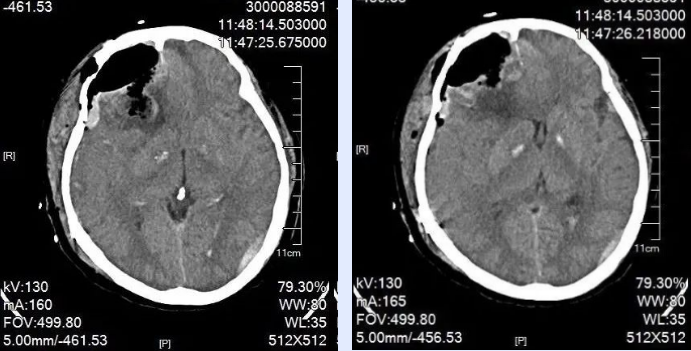

患者入院时已出现神志不清、嗜睡、言语含糊等情况。入院后不久,患者病情进行性加重,神志昏迷,呼吸急促,瞳孔不等大,对光反射迟钝,生命垂危,复查头颅CT,结果显示硬膜下血肿、脑内血肿出血急剧增多,中线移位明显,需立即行手术治疗。

时间就是生命,速度决定安危,准确研判患者伤情后,在麻醉手术科的配合下,我院神经外科贺喜武手术团队积极行手术抢救,术后,经ICU 20余天全力救治,患者最终转危为安。后期恢复远超预期,与摔伤前无异,神经外科团队高超的救治水平得到患者及家属的一致认可。